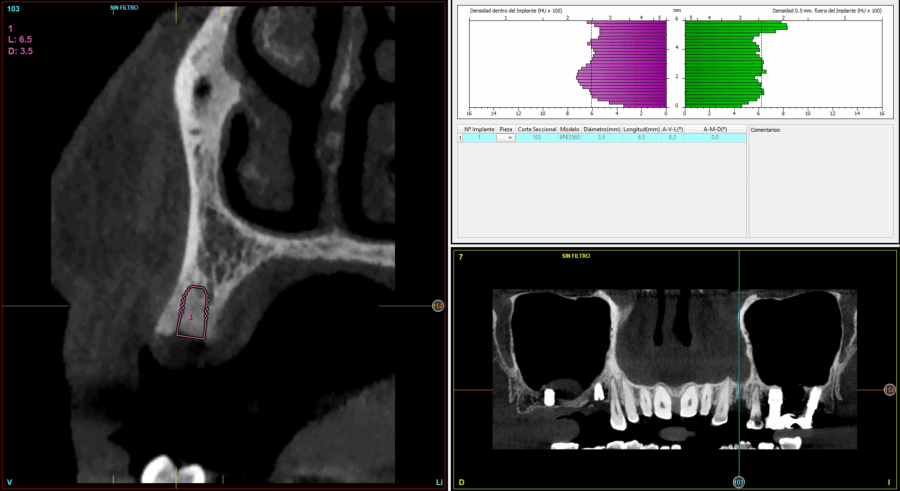

En cuanto a la rehabilitación protésica, en todos los casos se utilizó una prótesis atornillada con transepitelial para prótesis unitaria. La supervivencia de las prótesis fue del 100%, sin encontrarse fracaso en ninguna de ellas al igual que los implantes, con un tiempo de seguimiento de tres años. Durante el primer año, en las visitas de control, ninguno de los implantes mostró sangrado al sondaje ni inflamación de los tejidos periimplantarios. La media de la pérdida ósea en este punto fue de 0,32 mm (+/- 0,60) y la media de la pérdida ósea distal de 0,31 (+/- 0,48). A los dos años, no se registraron tampoco signos inflamatorios en ninguno de los implantes y la pérdida ósea mesial del conjunto fue de media de 0,38 mm (+- 0,54) y la distal de 0,64 mm (+/- 0,70). En la última visita a los 3 años, los tejidos periimplantarios siguieron estables, sin signos de inflamación y la media de la pérdida ósea mesial fue de 0,40 mm (+/- 0,53) y la distal de 0,69 (+/- 0,55) (Figura 5). En las Figuras 6-12 se muestra uno de los casos incluidos en el estudio.